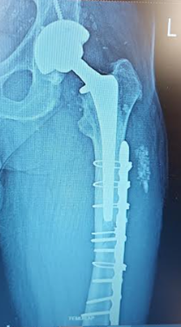

Initial fracture, fixation, and broken hardware